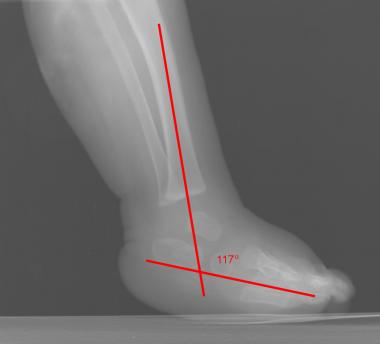

Talocalcaneal angle(30-55도, dorsiflexion lat시 25~50도) 이나 Talo-1st MT angle(5-15도), tibiocalcaneal stress lateral angle(10~40도) 를 시행해 볼 수 있습니다.

Tibiocalcaneal stress lateral angle 은 만곡족에서는 음각입니다.